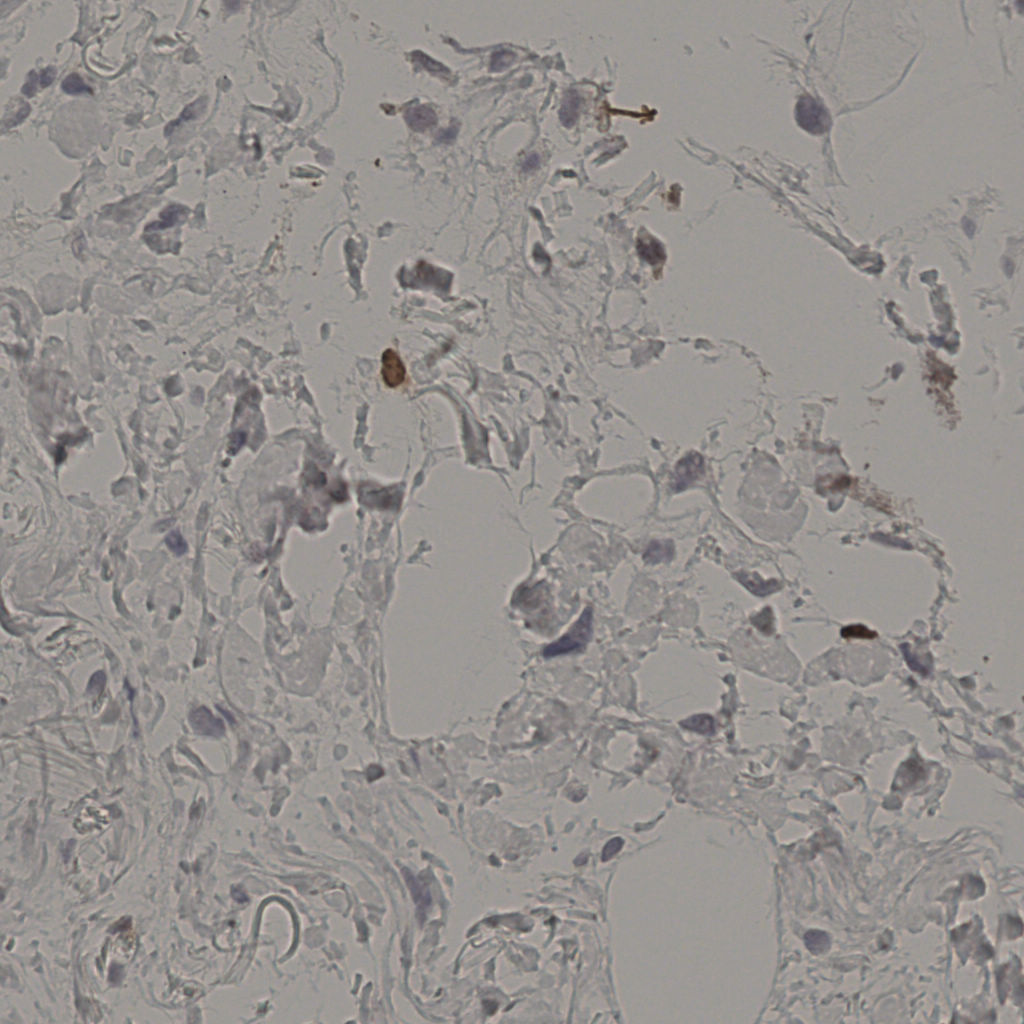

17.75%

Ki67 指数

阴 7986

阳 1723

切片统计

总切片

2640

有效

412

已标记

412

有效率

16%